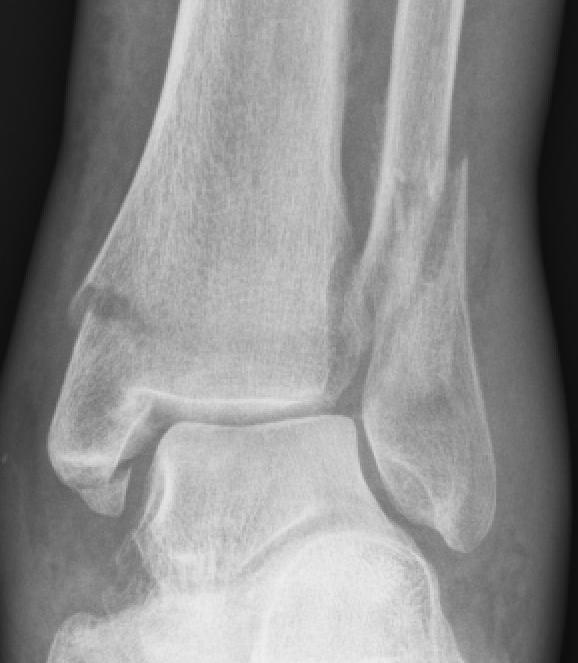

Ankle Fractures Core EM